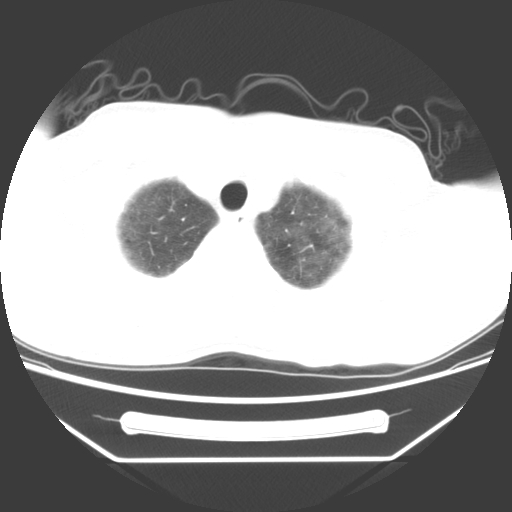

病人55岁,咳嗽,胸闷

忘了传病史了,病人55岁,咳嗽,胸闷

两肺部呈“毛玻璃”状改变,原因待查考虑感染性病变

病人是否发烧,两肺“磨玻璃”影,其间见空气支气管征和碎路石征。考虑肺泡蛋白沉着症。

两肺广泛对称磨玻璃样影,密度不均,考虑机遇性肺部感染。

双肺弥漫磨玻璃样病变,病史很重要。有感冒或发烧史,甲流不除外。无发烧可考虑肺泡蛋白沉积,但肺泡蛋白沉积边缘往往较清晰,与正常肺组织分界清晰

两肺弥漫间质性病变,考虑肺泡蛋白沉着症。建议进一步检查。